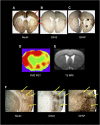

As a sequel of brain ischemia, selective neuronal loss (SNL)-as opposed to pannecrosis (i.e. infarction)-is attracting growing interest, particularly because it is now detectable in vivo. In acute stroke, SNL may affect the salvaged penumbra and hamper functional recovery following reperfusion. Rodent occlusion models can generate SNL predominantly in the striatum or cortex, showing that it can affect behavior for weeks despite normal magnetic resonance imaging. In humans, SNL in the salvaged penumbra has been documented in vivo mainly using positron emission tomography and (11)C-flumazenil, a neuronal tracer validated against immunohistochemistry in rodent stroke models. Cortical SNL has also been documented using this approach in chronic carotid disease in association with misery perfusion and behavioral deficits, suggesting that it can result from chronic or unstable hemodynamic compromise. Given these consequences, SNL may constitute a novel therapeutic target. Selective neuronal loss may also develop at sites remote from infarcts, representing secondary 'exofocal' phenomena akin to degeneration, potentially related to poststroke behavioral or mood impairments again amenable to therapy. Further work should aim to better characterize the time course, behavioral consequences-including the impact on neurological recovery and contribution to vascular cognitive impairment-association with possible causal processes such as microglial activation, and preventability of SNL.